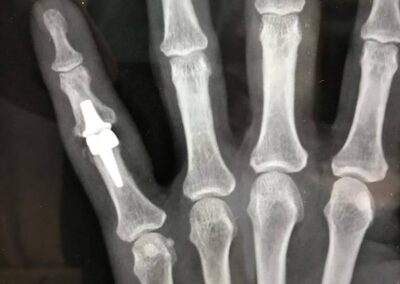

Cemented SR Cobalt Chrome with polyethylene cemented SR Arthroplasty

Finger Joint Arthritis and Joint Replacement Arthroplasty – Case 5

Cemented SR Cobalt Chrome with polyethylene cemented SR Arthroplasty via volar approach for post-traumatic arthritis with deficient volar plate and swan deformity.